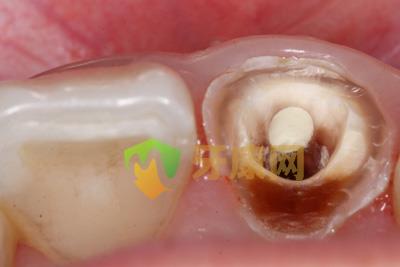

MTA修補后